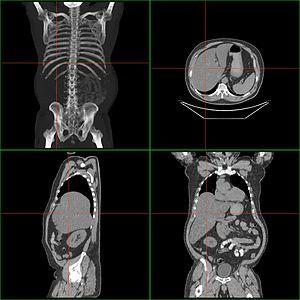

Computerized tomography of hepatomegaly

Computerized tomography (CT) can help to obtain accurate anatomical information, in individuals with hepatomegaly for the purpose of a complete diagnosis.[21]